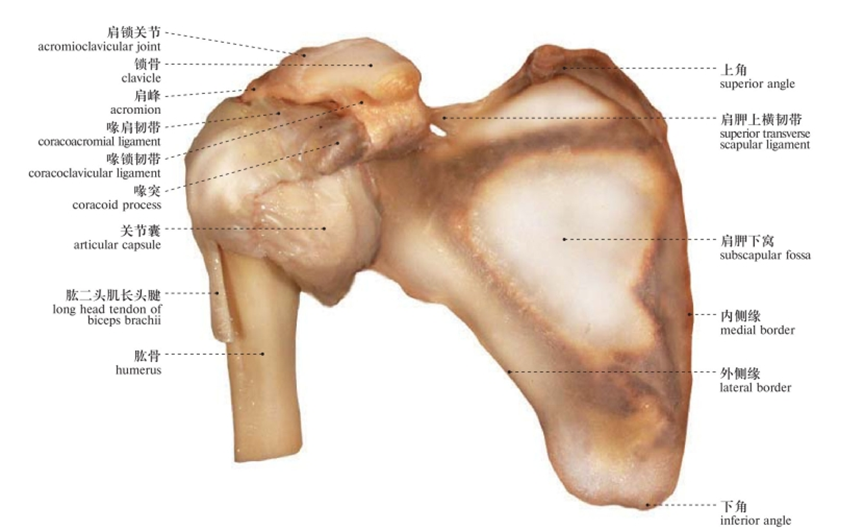

肩关节的连结

肩锁关节(AC):锁骨远端与肩胛骨肩峰突的交汇点。

胸锁关节(SC):锁骨近段与胸骨 、第一肋的交汇点。这是一个相对较小的关节,它起到了连结肩臂与中轴骨(胸廓)的作用。

盂肱关节(GH):肱骨的球面端嵌入肩胛骨关节窝所形成的凹面;大部分人会认为盂肱关节就是“肩关节”。

肩胛骨-胸廓关节(ST):严格来说它并不是一个关节(关节的定义是两块骨骼的交汇点),而是肩胛骨与胸廓后外侧的接触位置。一块肩胛骨通过17块肌肉的协同作用,与肱骨共同完成动作(灵活性),同时也为理想的体资及过顶动作创造足够的支撑(稳定性)